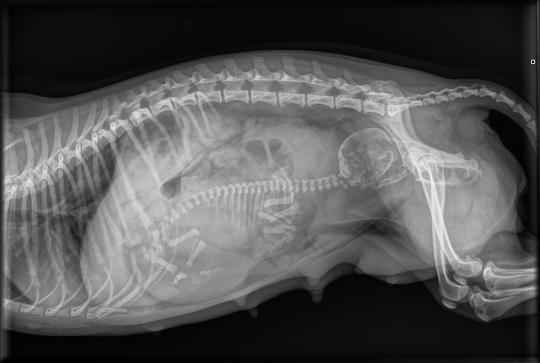

Im Röntgen ist der zweite Fötus in sogenannter Vorderendlage (Kopf gegen hinten) zu sehen. Er erscheint eher gross, andererseits hatte Peach mit der Geburt des ersten Welpen keine grösseren Probleme gezeigt. Der nächste Schritt wäre eine Beurteilung des Föten mittels Ultraschall - je nach dessen Herzfrequenz kann allenfalls noch abgewartet und auf eine natürliche Geburt gehofft werden.